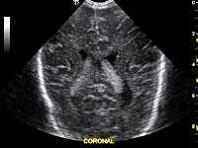

图中脑室内高回声区域为?(?)A.室管膜下出血B.脉络丛C.肿瘤D.脑室出血E.脑室扩张

问题 图中脑室内高回声区域为?(?)

选项 A.室管膜下出血 B.脉络丛 C.肿瘤 D.脑室出血 E.脑室扩张

答案 B